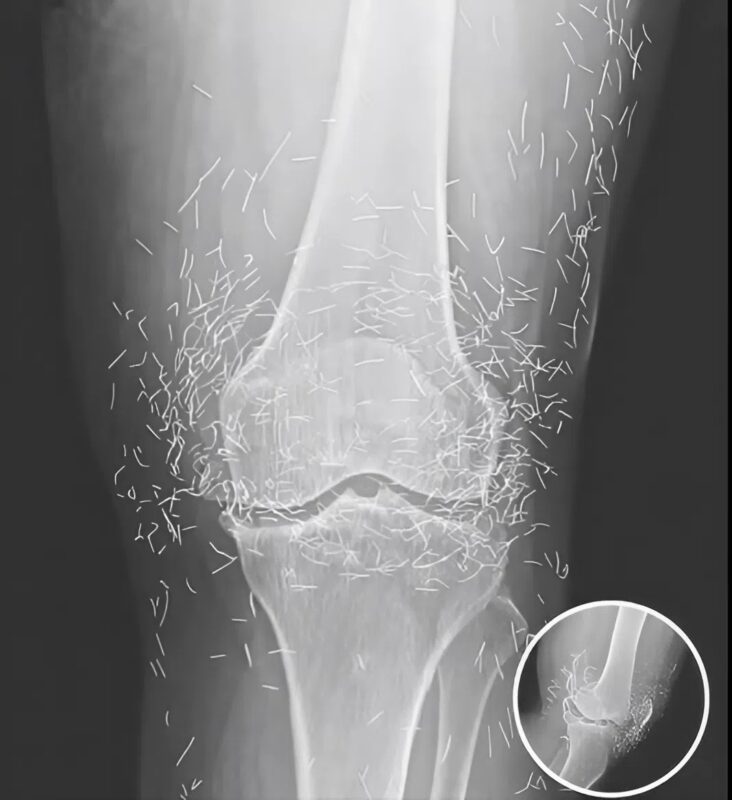

When the images arrived, everything changed. The nurse who brought them in froze by the door. “Doctor… you need to see this.” I took the envelope, pulled out the film, and held it against the light. For a second, I couldn’t comprehend what I was looking at. Her knee joint shimmered with dozens of tiny, metallic streaks — arranged in perfect symmetry.

At first, I thought it was an error — maybe a reflection, a machine glitch. We repeated the scan. The same strange pattern appeared again. I adjusted the magnification, leaned closer to the screen… and then felt a chill run down my spine. Those streaks weren’t reflections. They were real. They were inside her. 😱

When she finally came to us, the inflammation was advanced. The X-rays showed what her faith had hidden: over thirty golden needles embedded in soft tissue, surrounded by infection and scar. The body had fought them all these years — forming capsules of fibrous tissue around each invader, as if building tiny prisons inside her flesh. But some capsules had ruptured, releasing toxins.

We scheduled emergency surgery. Under anesthesia, I studied her knee one last time on the monitor. The needles sparkled like constellations — Orion, Cassiopeia, stars trapped beneath her skin. 🌌 The image was hauntingly beautiful and unbearably tragic.